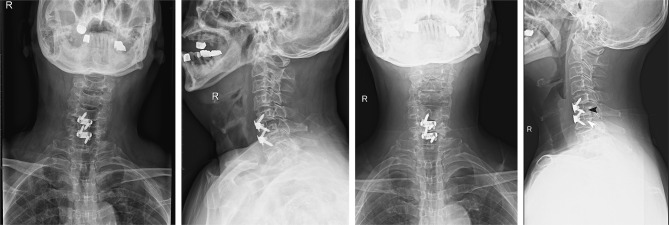

Purpose: The aim of this study was to explore short-term radiological findings after contiguous two-level ACDF with Zero-P VA devices.

Methods: Patients who underwent contiguous two-level anterior cervical discectomy and fusion (ACDF) from C3 to C7 with a Zero-P VA system were followed. Cervical anteroposterior and lateral X-rays and functional outcomes were assessed 3 months after surgery.

Results: Overall, 34.9% of patients had prosthesis subsidence and 74.6% screw loosening. Up to 46.8% of the patients with screw loosening also experienced prosthesis subsidence compared with 0 patients without screw loosening (p=0.0005). The screw-loosening rate was 91.7% in patients with poor positioning of the screw/cage and 70.6% in patients without poor positioning of the screw/cage, but no statistical difference was found between the groups (p=0.267). The subsidence rate was 50% in patients with poor positioning of the screw/cage and 31.4% in patients without poor positioning of the screw/cage, but no statistical difference was found between the groups (p=0.314). VAS scores of patients with prosthesis subsidence were much higher than those without (p=0.031), but this difference was not found for patients with or without screw loosening (p=0.116). The NDI scale was much higher in patients regradless of screw loosening or subsidence.

Conclusion: Screw loosening and prosthesis subsidence happen frequently after contiguous two-level ACDF with Zero-P VA. Screw loosening seems to be the only risk factor for prosthesis subsidence.